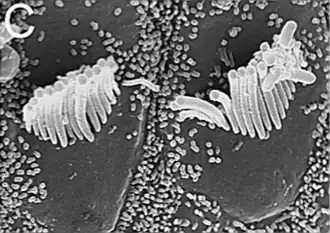

La cóclea[1] (del latín cochlea, también conocida como caracol) es como se denomina a la lágena en mamíferos porque aparece enrollada en espiral. Se sitúa en el oído interno. En su interior se encuentra el órgano de Corti, que es el órgano del sentido de la audición. Está dotado de células ciliadas que poseen estereocilios capaces de transformar las vibraciones del sonido en impulsos nerviosos que son enviados hasta el cerebro.

Estas tres cámaras están separadas por dos membranas: la membrana de Reissner, entre la rampa vestibular y la rampa media o coclear; y la membrana basilar, entre la rampa media o coclear y la rampa timpánica. Es en la membrana basilar donde descansa el órgano de Corti con las células ciliadas (que son los receptores auditivos). El eje en torno al cual se enrolla la cóclea se conoce como modiolo o columela. Junto a él está el ganglio espiral de Corti de donde parte el nervio auditivo (VIII par craneal).[5]